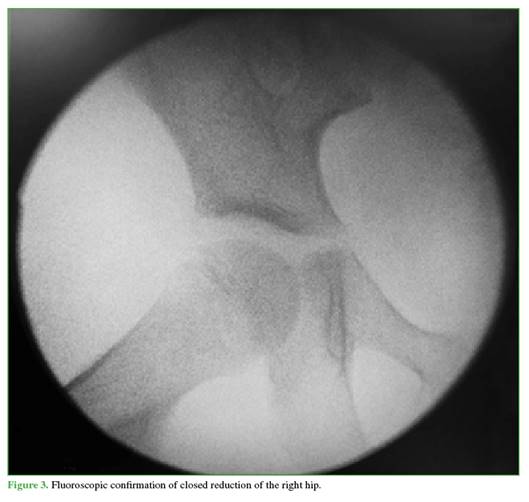

After stabilization, closed reduction under sedation was performed 8 hours after the accident. With the child in the supine position and the knee flexed at 90°, longitudinal traction was applied; simultaneously, the proximal femur was displaced laterally using a strap and external rotation, achieving successful clinical reduction. Stability maneuvers were positive, and reduction was confirmed by fluoroscopy (Figure 3).